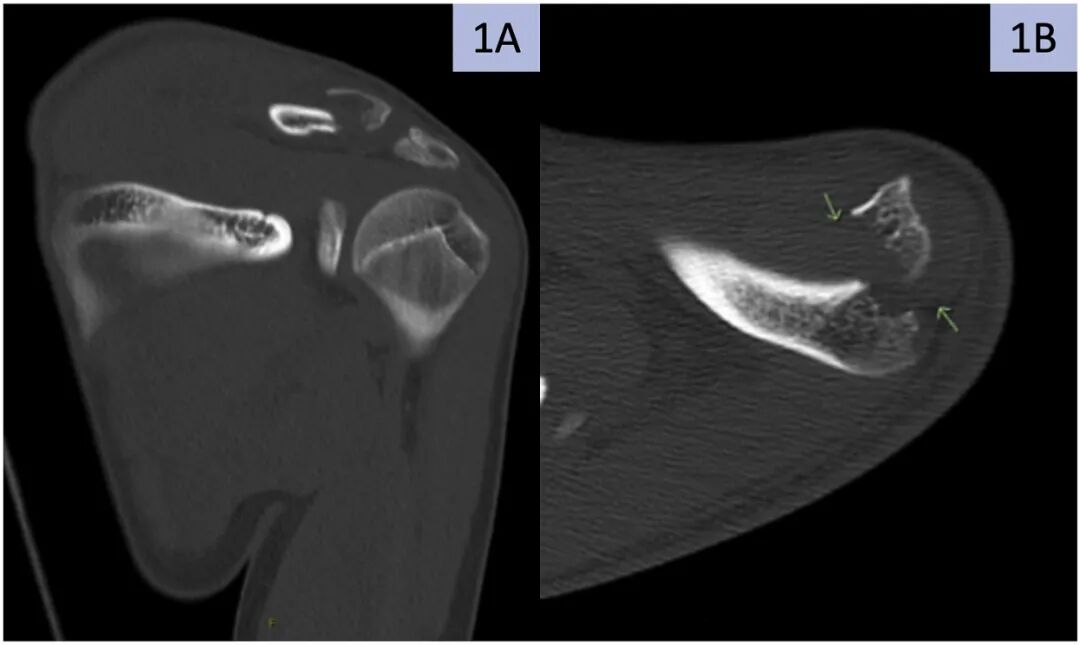

手术后

手术后,将手臂置于吊带中6周以避免潜在的移位,并允许肩摆。手术后6周开始进行温和而渐进的活动范围程序。术后3个月,完全愈合(图5),患者表现出完全的力量,正常的轮廓和对侧肢体的平等运动(前屈180,伸展45,外旋和内旋100°和20° 手臂分别外展至90°,内旋至T6)。在1年的随访中,患者肩部功能极佳,Marx肩部评分为1分,满分20分,18分,手臂、肩部和手部残疾(QuickDASH)评分为0分(表明没有残疾)。

图5。远端锁骨骨折缝合固定3个月后拍摄的X光片。A)前后位和B)头侧倾斜视图。注意这个时间间隔的完整骨结合。

在本病例报告中,我们提供了一种简单且资源较少的方法来治疗老年儿科患者的远侧锁骨远端骨折,避免了可能需要第二次手术移除的植入物突出和疼痛的风险。我们的患者在手术后3个月完全恢复功能,放射学愈合。